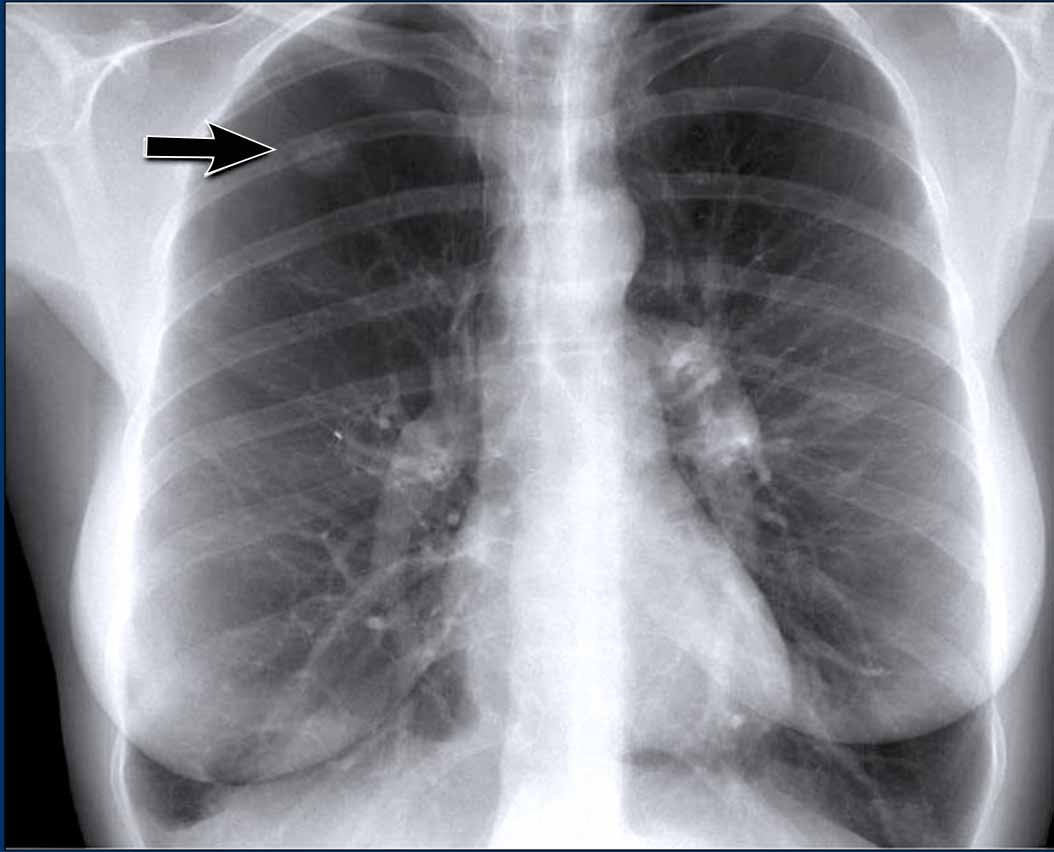

Vena azygos lobe, seen as a fine line that crosses the apex of the right lung. Vena azygos lobe, seen as a fine line that crosses the apex of the right lung.

Vena azygos lobe

A common normal variant, the azygos lobe, is formed when the azygos vein takes an anomalous lateral course, creating a deep pleural fissure in the upper lobe of the right lung.

On radiographs, it appears as a thin curvilinear line traversing the right upper lung field, frequently ending in a teardrop-shaped density (the azygos vein) within the azygos fissure.

Here another patient with an azygos lobe.

The azygos vein is seen as a thick structure within the azygos fissure.